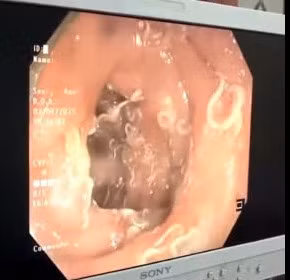

| Nội soi phát hiện hàng trăm con giun "trú ngụ" trong đường tiêu hóa người phụ nữ, gây suy kiệt. Ảnh BVCC |

Kết quả nội soi cho thấy, thành tá tràng có của người bệnh có những con giun móc rất nhỏ bám chặt. Tại khu vực trực tràng, đại tràng, rất nhiều con giun tròn màu trắng bám ở niêm mạc, có những chỗ giun cuộn vào nhau tạo thành búi. Niêm mạc đại tràng toàn bộ bị phù nề, xung huyết, có chỗ rỉ máu. Sau 10 ngày điều trị, sức khỏe của người bệnh đang dần ổn định.